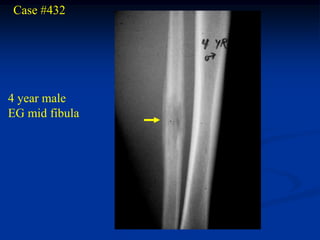

Case #432

4 year male

EG mid fibula